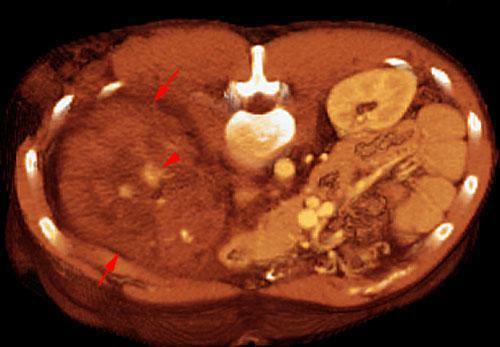

Estallido renal

VR seccional. Visión axial cenital. AngioTC aórtico mostrando un gran hematoma perirrenal (flechas). Se visualizan pequeños fragmentos contrastados del parenquima renal (punta de flecha)